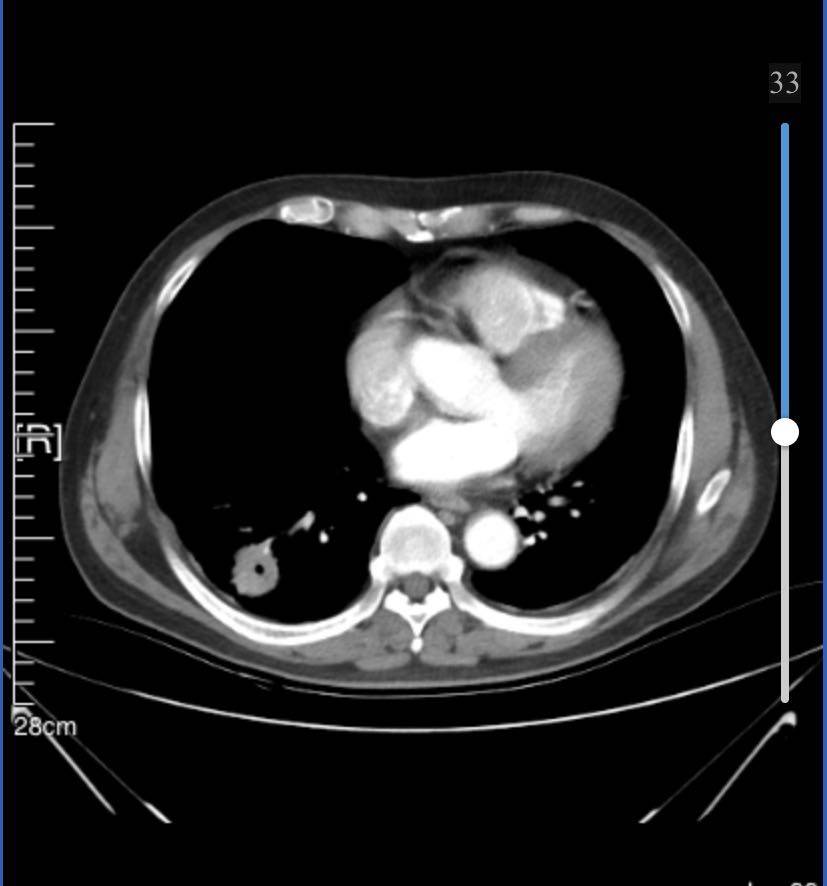

8月21日胸ct显示右肺下叶占位,3.4cm*3.0cm,纵隔及右肺门多发增大淋巴结;右前肋胸膜外脂肪间隙内淋巴结肿大;左肺上叶磨玻璃结节1.6cm,微浸润性腺ca。

目前已经服药1个月,10月23号拍ct,右下肿瘤2.4*2.5,淋巴结略有缩小,磨玻璃结节1.4…